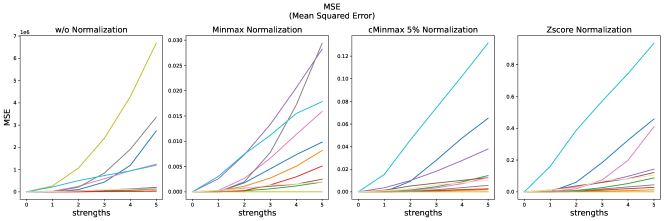

The results for all strengths are given in Figs. A.1-A.4. In Tab. 5 - 8, the results for distortions of maximal strength (s=5) are summarized.

For all applied distortions, all reference metric scores monotonously measure lower similarity for increasing distortion strengths.

Without applying any normalization, all metrics beside NMI are very sensitive to intensity shifts (see Tab. 5). However, with any normalization method, intensity shifts are fully compensated, and all metrics measure perfect similarity.

All error metrics (MSE, MAE and NMSE) strongly vary in their value range, depending on the normalization method. They are consistently most sensitive to translation and then to bias field, and gamma transforms. As cMinMax partially compensates the effect of the gamma transforms, the error metrics hardly find dissimilarities in the gamma transformed images with this normalization.

The experiments and adverse examples demonstrate specific strengths and weaknesses of the analyzed metrics. Although SSIM and PSNR are frequently used for the evaluation of synthetic MR images, they are strongly decreased by constant intensity shifts if no normalization is applied. PSNR is very dependent on the kind of normalization, which complicates its use as a comprehensive metric for comparing studies of different authors. SSIM underestimates blurring and thereby favors blurred or additionally blurred images over other distortions.